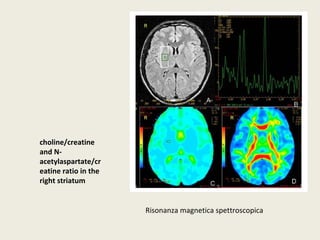

PATTERN NEUROFUNZIONALI EBRAIN IMAGING NEI DISTURBI DELLO SPETTRO AFFETTIVO da Blumberg et al., 2003 fRMN: Anomalie fronto-striatali in soggetto con DB

Risonanza magnetica spettroscopica choline/creatine and N-acetylaspartate/ cr eatine ratio in the right striatum

Spettroscopia Protonica 1H- MRS C DB da Brady et al., 2012 PATTERN NEUROFUNZIONALI E BRAIN IMAGING NEI DISTURBI DELLO SPETTRO AFFETTIVO Voxels: corteccia cingolata anteriore (ACC) – corteccia parietale occipitale (POC) Plots 2D: lattato